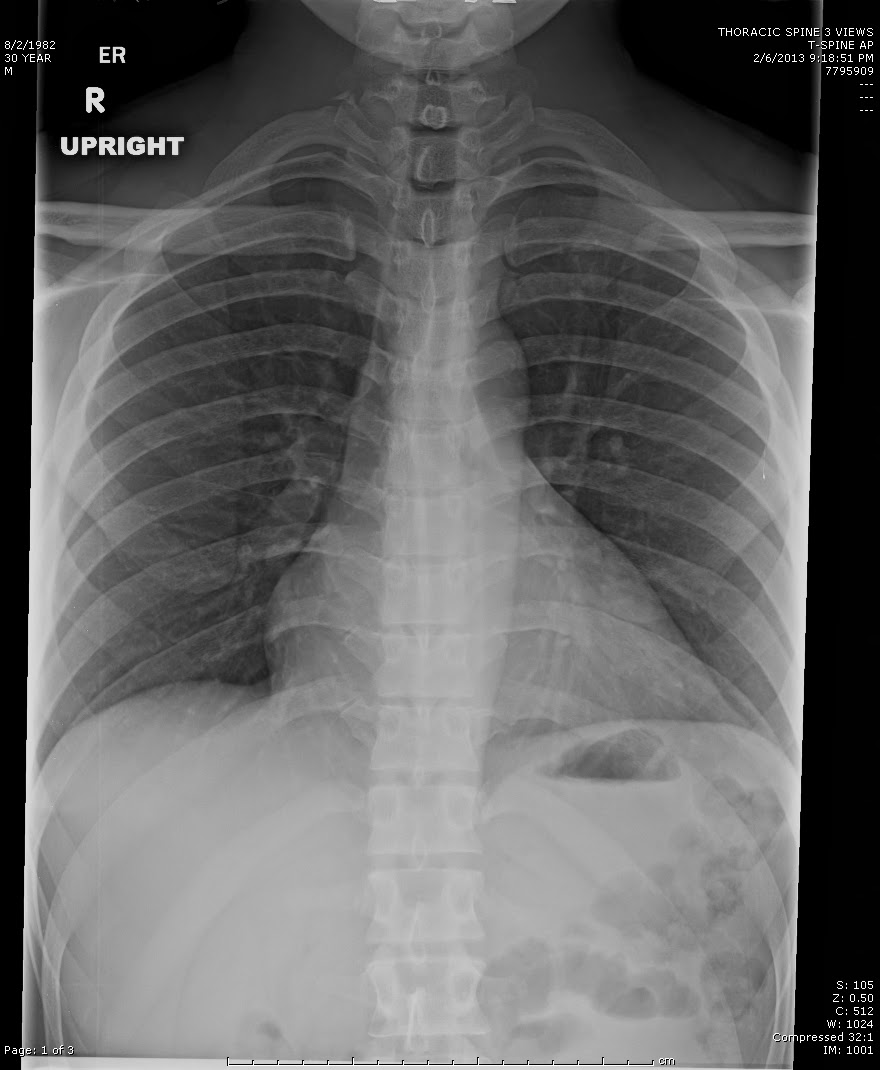

La tele de tórax y la radiografía convencional son estudios por rayos X que ofrecen imágenes de la cavidad torácica, pero presentan diferencias técnicas y clínicas importantes. Ambos exámenes evalúan pulmones, corazón, pleuras y estructuras óseas, pero la tele de tórax se caracteriza por proyecciones específicas y un calibre de detector diseñado para optimizar la visualización del tórax completo. En cambio, la radiografía normal puede referirse a cualquier placa simple en posición genérica, sin protocolos de proyección estandarizados para patología torácica.

thoracic radiographyLa tele de tórax emplea un foco a detector de gran distancia (al menos 1.8 metros) que reduce la distorsión de la silueta cardíaca y mejora la resolución de los detalles pulmonares. La radiografía simple o “normal” suele realizarse con distancias foco-película menores, adaptadas a exploraciones generales (columna, abdomen, extremidades). En la práctica clínica, la tele de tórax se realiza con valores de kilovoltaje más altos (110–120 kVp), lo que permite una penetración adecuada y un contraste óptimo entre tejidos blandos y aire.

Proyecciones y posicionamiento

En la tele de tórax, las proyecciones estándar son posteroanterior (PA) y lateral, garantizando una visión bidimensional completa. El paciente se posiciona de pie, hombros rotados hacia adelante, con inspiración máxima sostenida, favoreciendo el descenso del diafragma y la máxima aeración pulmonar. La radiografía normal puede carecer de estas especificaciones: a menudo se obtiene una única proyección anteroposterior (AP), incluso en decúbito, lo que produce aumento aparente del tamaño cardíaco y reduce la visibilidad de estructuras posteriores.

Calidad de imagen y detalle anatómico

La tele de tórax provee un mayor nivel de nitidez y menor distorsión de la silueta cardíaca, facilitando la identificación de infiltrados, cavitaciones o nódulos pulmonares. Además, el uso de detectores digitales de alta resolución mejora el escalado de grises y permite postprocesamiento de imágenes. Por su parte, la radiografía convencional en proyección única puede presentar menor contraste y resolución, siendo suficiente para evaluaciones rápidas de fracturas costales o posicionamiento de dispositivos, pero menos precisa para diagnóstico pulmonar detallado.

Aunque ambas técnicas usan la misma fuente de radiación, la tele de tórax optimiza dosis a través de la configuración PA, reduciendo exposición directa a órganos sensibles como la mama y el tiroides. La radiografía normal, en proyección AP, puede implicar dosis ligeramente superiores en estructuras anteriores. En cuanto a accesibilidad, la placa torácica se ofrece en prácticamente todos los servicios de urgencias y consultas externas; la radiografía genérica está disponible en unidades móviles o de cabecera.

Indicaciones clínicas y limitaciones

La tele de tórax se recomienda ante sospecha de neumonía, tuberculosis, derrame pleural, neumotórax, cardiomegalia o seguimiento de EPOC. Su estandarización la convierte en el estudio de elección inicial para patología torácica. La radiografía normal tiene indicaciones más amplias y rápidas, ideal para pacientes encamados o valoraciones generales fuera del contexto pulmonar. Ninguno de los dos reemplaza estudios avanzados como tomografía computarizada cuando se requiere investigación de lesiones pequeñas o mediastínicas profundas.